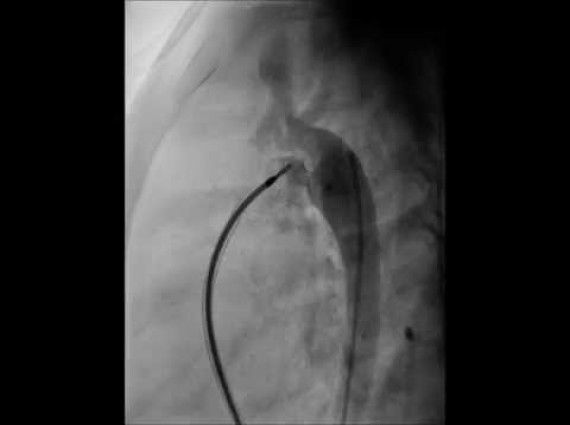

Son zamanlarda bazı doğuştan kalp hastalıklarının kesin tedavisinde, bazılarının palyatif tedavilerinde girişimsel tedavi yöntemleri ön plana çıkmıştır. Kalp kateterizasyonu / anjiyografi yöntemiyle uygulanan bir tedavi yöntemidir.

İşlemler cerrahiye göre kısa sürmekte, daha az komlikasyon ve daha az hastane kalış süreleri olmaktadır. Kalp durdurulmamakta, çoğunlukla herhangi bir kan transfüzyon ihtiyacı gerektirmemektedir. Vücutta herhangi bir kesi veya skar (ameliyat izi) oluşmamaktadır. Yoğun bakım ihtiyacı çok az vakada gerekmektedir. Kalpteki delikler, kapak yada damarlardaki darlıklar, suni kapak yerleştirmeleri dahil birçok işlem girişimsel tedavi yöntemiyle mükemmel bir şekilde uygulanabilmektedir. Birden fazla ve farklı patolojileri olan kalp hastalıklarında aynı seansta girişimsel tedavi uygulamaları gerçekleştirilebilmektedir.

Girişimsel tedavi seçenekleri ve çeşitliliği giderek artmakta doğuştan kalp hastalıklarının %80’ine uygulanabilmektedir.